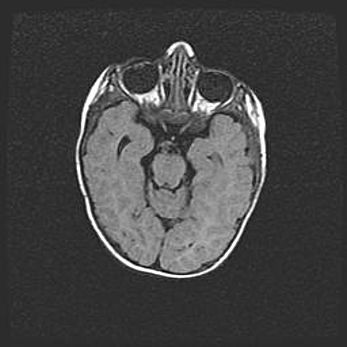

Множественные кисты обоих полушарий головного мозга, наибольшая из них в правой затылочной области. Ассиметричная атрофическая гидроцефалия.

Возраст: 7 месяцев

Вес: 5660 г

Пол: мужской

Окружность головы: 41,5 см

Срок гестации: 28-29 недель

Кисты головного мозга развиваются в результате многоочаговых некрозов вещества мозга и возникают вследствие перенесенной перинатальной инфекции, менингитов, энцефалитов, асфиксии, родовой травмы, расстройств мозгового кровообращения различного генеза. Образованию кист в веществе головного мозга плодов и новорожденных способствуют такие факторы, как высокое содержание в нем воды, недостаточная (или отсутствие) миелинизация и слабая астроглиальная реакция на повреждение.

Кисты могут сочетаться с гидроцефалией и другими поражениями головного мозга.